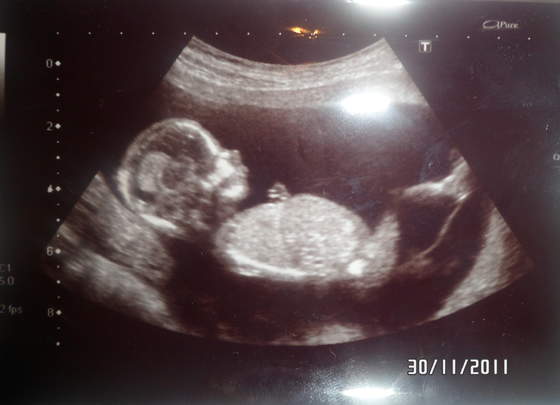

a to jeden na drugim asiia gratulacje, nie wiem co Ci powiedziała Polska gin ale niezależnie czy to bliźniaki jednojajowe, czy dwujajowe mogą być tej samej płci, np. moi chłopcy są dwujajowi, po prostu nie są identyczni.